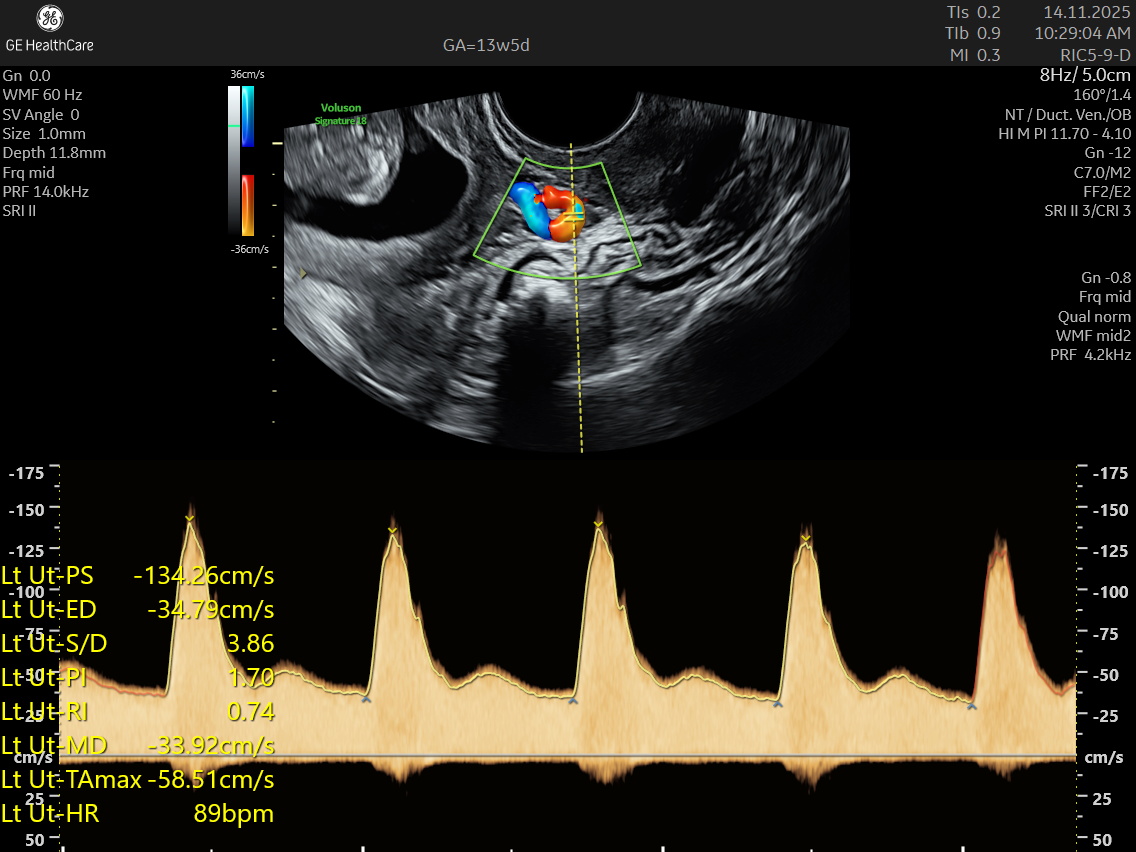

NESA Institute of Fetal Medicine offers specialized first-trimester screening for expectant parents, delivering high-precision NT scans between 12 to 13 weeks of pregnancy. Our experienced fetal medicine team ensures accurate risk assessment for chromosomal abnormalities, including Down syndrome, Edwards syndrome, and Patau syndrome.

The NT scan is a non-invasive ultrasound examination conducted in the first trimester (12–13 weeks). It measures the nuchal translucency (the fluid at the back of the fetus’s neck) and combines it with the maternal blood test for a detailed risk profile. NT Scan is an important early screening test for Down syndrome (Trisomy 21), Edwards syndrome (Trisomy 18), and Patau syndrome (Trisomy 13).

Although the NT scan is mainly a screening tool and not diagnostic on its own, it can identify about 50% of major fetal abnormalities when combined with other assessments like blood tests and detailed ultrasound. The scan also helps to screen some basic anatomical structures during the first trimester, especially the fetal heart anatomy, brain, face, spine, stomach, abdominal wall, kidneys, bladder, and extremities to varying degrees depending on gestational age and maternal factors.